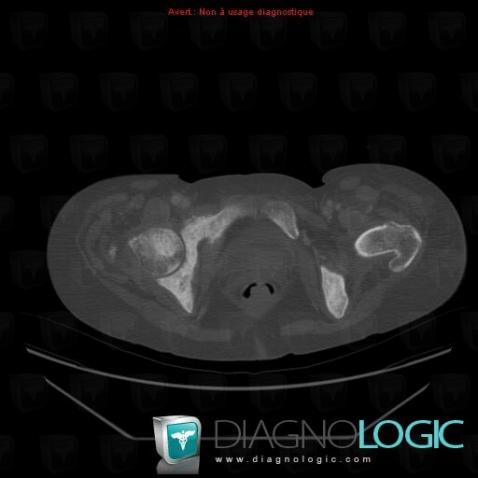

Metastasis, Ilium, CT

Here is the specific information in the key image above:

- Diagnosis Metastasis, Location(s) Ilium, with gamuts Multiple osteosclerotic bone lesions